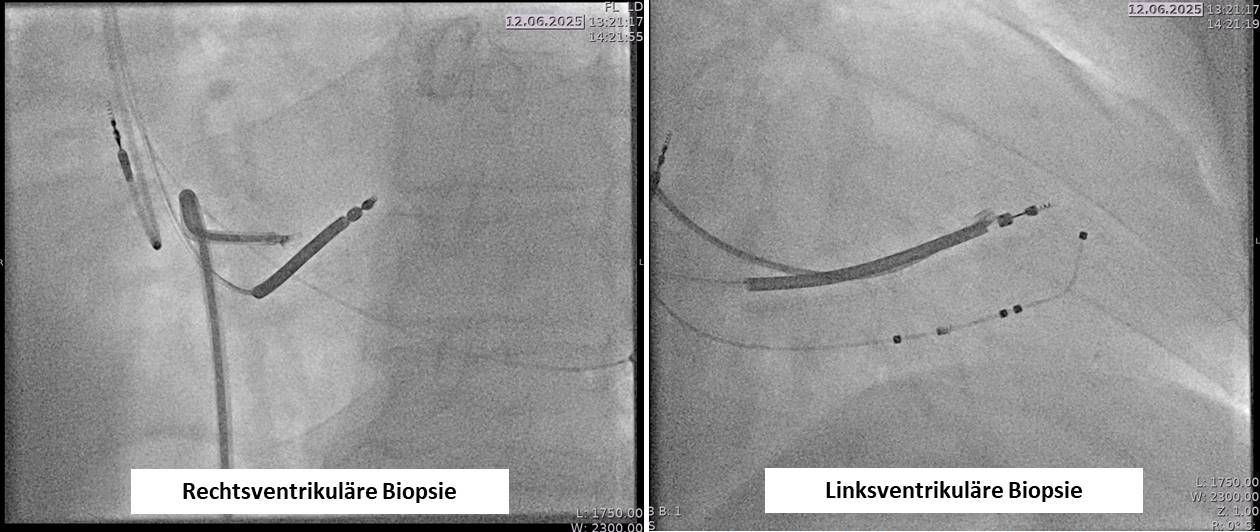

Die interventionelle Myokardbiopsie ist ein diagnostisches Verfahren zur Entnahme kleiner Gewebeproben aus dem Herzmuskel. Sie dient der Abklärung unklarer Herzerkrankungen, insbesondere bei Verdacht auf Myokarditis, infiltrative oder genetische Kardiomyopathien sowie zur Abstoßungskontrolle nach Herztransplantation.

Der Eingriff erfolgt in der Regel über die rechte Vena jugularis oder die Vena femoralis. Unter Röntgen- und Echokardiokontrolle wird ein spezieller Katheter (Bioptom) in den rechten Ventrikel eingeführt. Dort werden mehrere kleine Proben aus dem Myokard entnommen, meist aus dem interventrikulären Septum. In bestimmten Fällen – z. B. bei isolierten linksventrikulären Veränderungen – kann auch eine linksventrikuläre Biopsie über die Arteria femoralis durchgeführt werden.

Angiographische Darstellung einer rechts- und linksventrikulären Biopsie.